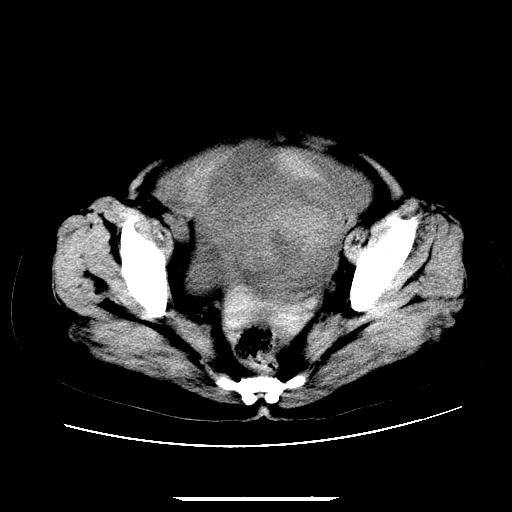

f,45y.怀孕4月晕倒,b超提示死胎,有手术结果,请展开讨论后明天告诉。

膈下-肠间隙内见气体密度影,子宫轮廓显示不清,宫腔-腹腔积液,首选考虑---子宫破裂出血。

1)宫腔妊娠。2)子宫破裂出血,腹腔及盆腔积血。

感谢同行们的高见。手术结果:子宫破裂出血。

我们的诊断是:腹、盆腔积液(考虑腹盆腔脏器破裂出血);宫腔妊娠。让人纳闷的是当时我们没有经验,现在回头看看分析:4月宫腔妊娠:1、洋膜囊不可能紧贴胎体这么小;2仔细看看子宫后壁肌层模糊不清;3腹、盆腔液体来源原因?4、45岁高龄妊娠有晕倒。由此可大胆诊断:宫腔妊娠子宫破裂出血。